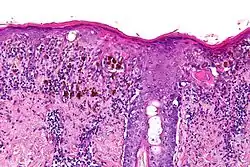

Czerniak guzkowy w obrębie twarzy

Obraz histopatologiczny czerniaka guzkowego

Czerniak guzkowy

Jest to drugi co do częstości podtyp czerniaka, stanowi około 10–15% wszystkich przypadków czerniaka[87][82]. Charakteryzuje się pionowym wzorcem wzrostu. Czerniak guzkowy może występować w dowolnym miejscu, w porównaniu do czerniaka szerzącego się powierzchownie częściej występuje na tułowiu, głowie, szyi i kończynach dolnych[87]. Klinicznie jest szybko rosnącym guzem[88]. Czerniak guzkowy najczęściej powstaje de novo, a znacznie rzadziej w istniejącym wcześniej znamieniu[89]. Nowotwór ten statystycznie częściej niż czerniak szerzący się powierzchownie dotyka osoby starsze[87].

Makroskopowo przedstawia się jako szybko rosnąca grudka lub blaszka. Zmiana bywa polipowata, a rzadko nawet uszypułowa. Guz jest symetryczny i dobrze odgraniczony, o gładkiej powierzchni[88]. Zmiana cechuje się kolorem czarnym lub niebieskim, możliwa jest postać amelanocytowa, która przybiera kolor różowoczerwony[87]. Rozmieszczenie barwnika często nie jest symetryczne, choć bywa regularne[88]. Często jest obecne owrzodzenie guza[87][90].

Mikroskopowo jest podobny do czerniaka szerzącego się powierzchownie, jednak nie obserwuje się horyzontalnego śródnaskórkowego rozprzestrzeniania się. Komórki nowotworowe znajdują się w skórze właściwej, komponenta naskórkowa jest zależna od obecności czerniaka w skórze właściwej i nie istnieje samodzielnie[88]. Pokrywający naskórek jest scieńczały, zamazany lub owrzodziały[87]. Guz jest zbudowany z masywnych gniazd melanocytów[91]. Wyróżnia się typy o komórkach przypominających komórki nabłonkowe, typ o komórkach wrzecionowatych i typ mieszany[92][90]. Melanocyty zwykle są pleomorficzne i często stwierdza się kilka typów komórek[88]. Mitozy są liczne, często obecna jest martwica atypowych melanocytów[91].